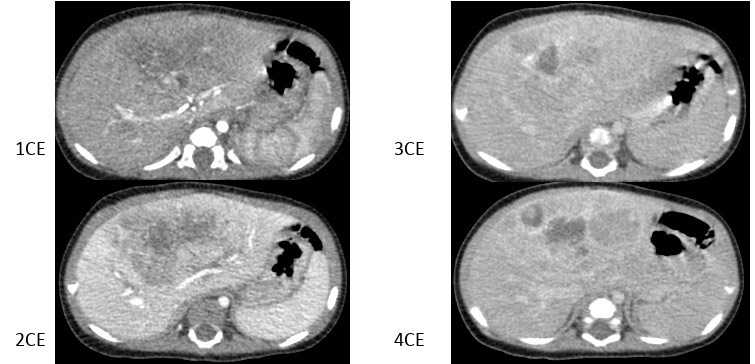

2969. Девочке 4 месяцев выполнена компьютерная томография брюшной полости с контрастным усилением, рентгенологическая картина соответствует